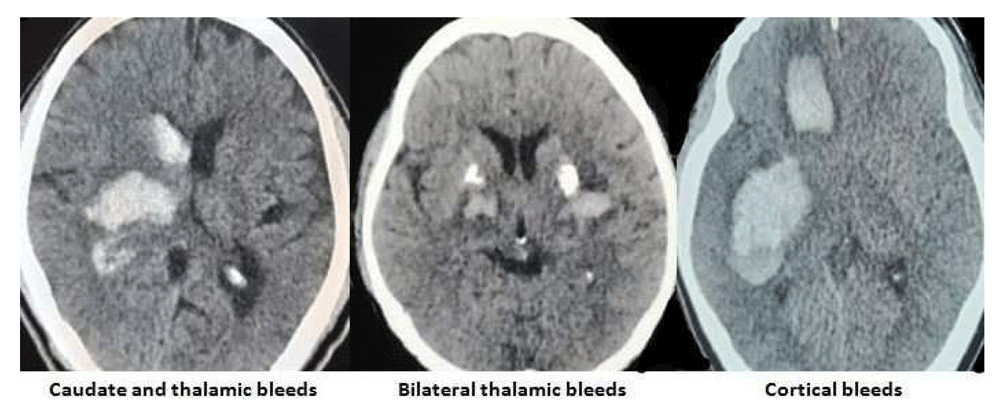

The images of the varied etiological causes of SMICH are demonstrated in the Figure 1–Figure 3.

All images are original, deidentified, and of our patients themselves.

Contrary to single ICH, SMICH significantly showed lobar territorial preponderance (Wu et al., 2017) (Renard et al., 2020). Our study had cortical-cortical patterns of involvement in 60% of the patients and basal ganglion and thalamic involvement in 12.5% of cases. Putamen and thalamus patterns of involvement were the most common anatomical patterns of involvement in a study by Yamaguchi et al. (2017) whereas bilateral thalamic hemorrhages variants were the most common in a study by Yen et al. (2005).